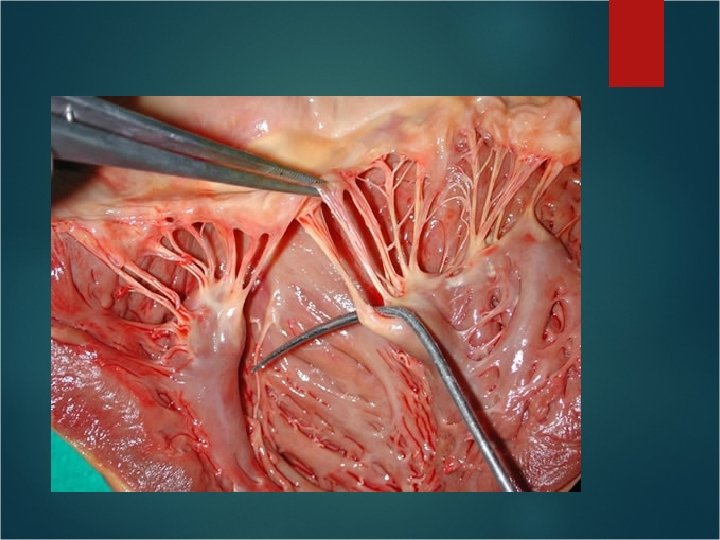

Valves of the Heart Atrioventricular valves (AV valves) lie between each atria and ventricle. Mitral valve – Left side; called bicuspid valve because it only has two flaps/cusps. Tricuspid valve – Right side; has three flaps Flaps are attached to ventricular wall by chordae tendineae.